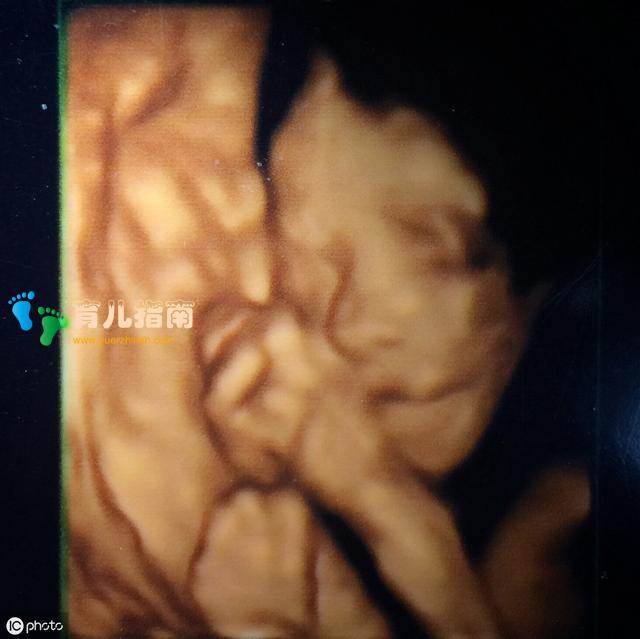

其实做四维彩超的时候,胎儿的嘴巴和鼻子会显得那么大,显得那么不对称,其实就是因为胎儿现在还没有足月,还没有发育成熟,这时候的胎儿身上会有胎脂,所以当我们透过照片看的时候,会感觉孩子的皮肤特别粗糙,而且鼻子和嘴巴看起来那么大。事实上,这和做四维时的拍照技术有着很大的关系,因为做四维彩超,它只是为了让医生们更加清楚的查看孩子发育有没有畸形的地方,因此四维彩超会显得模糊一些,会显得胎儿不那么好看。

医生给孕妈妈们做四维彩超时拍摄的那些照片,那只是胎儿的一个大概的模样,并不是说像我们现在这种高科技的手机那样,能对焦,能调光,能把人拍的那么漂亮。胎儿在子宫里的时候,因为有羊水,所以在拍摄的时候,照片会显得有些模糊变形。

不仅如此,胎儿在子宫里的时候,并非是像我们现在人拍照片一样乖乖的站在那里不动,胎儿可是会打嗝,会吃手指,会打哈欠,也就是因为胎儿一直在动,所以拍摄的照片也会受到一些影响。其实最主要的就是,拍摄四维照片的时候医生会把个别的地方放大来查看,所以拍摄的照片会显得嘴巴很大,鼻子也很大,让人看起来这个胎儿长的很丑。